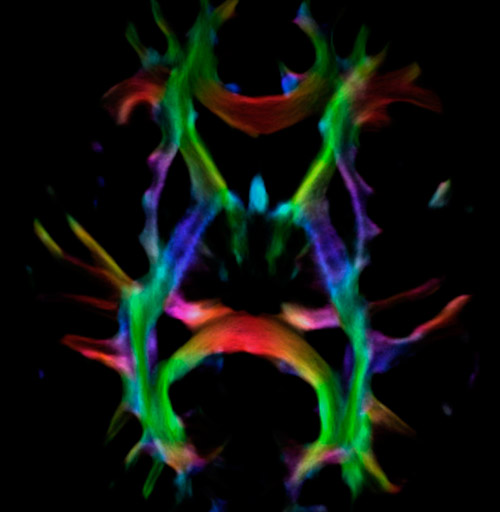

Fiber tractography of the corticospinal tract with seed region of the posterior limb of the internal capsule. Different processing based on the same data.

Fiber tracking from the left and right hippocampi to the fornix.

Fiber tracking from the left and right hippocampi to the fornix (green), and the corticospinal track based on a seed region of the posterior limb of the internal capsule.

All images were created from the same acquisition in a child using Ingenia 3.0T CX and 32-channel dS Head coil. Diffusion data was acquired at b-values 0, 500, 1000, 2000, 3000. The use of high b-values (3000 s/mm2) effectively suppresses extra-axonal water signal and provides high angular resolution.

Data processing was performed using open source software. Fiber tracking was performed using the MRtrix package (J-D Tournier, Brain Research Institute, Melbourne, Australia, https://github.com/MRtrix3/mrtrix3), Tournier et al. 2012. DEC TDI based on F Calamante et al 2010.